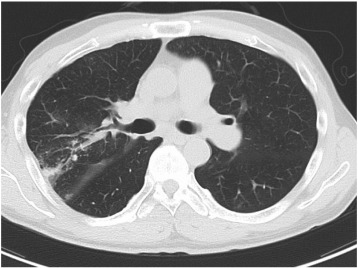

4 h after each BPA session, we took chest CT to evaluate incidence and location of RPI. RPI was defined when there was any increase in density (regardless of the size) observed on CT image in the corresponding pulmonary segment of the dilated pulmonary artery (Fig. 1). All CT images were analyzed by two independent observers who were blinded to all clinical information. When the two observers' decisions were inconsistent, a third observer analyzed the images for making the final decision.

Representative case of computed tomography imaging of the reperfusion pulmonary ...

Fig. 1.

Representative case of computed tomography imaging of the reperfusion pulmonary injury. (A) Chest CT image before the BPA. (B) Chest CT image 4 h after the BPA. During the BPA, the right pulmonary artery A10 was dilated, and the density of S10 increased during chest CT imaging as the reperfusion pulmonary injury occurred in S10. BPA: balloon pulmonary angioplasty, CT: computed tomography.